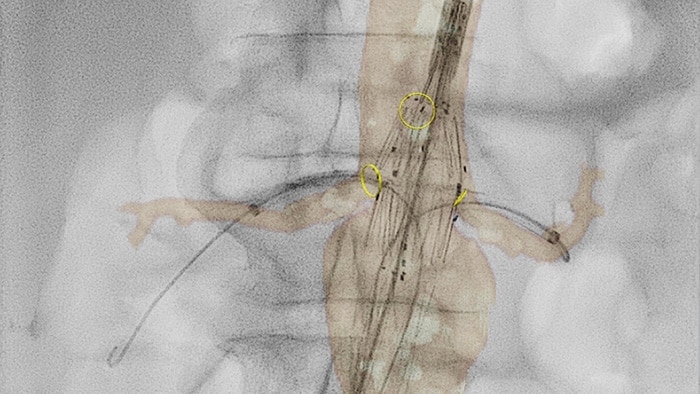

VesselNavigator permite la reutilización de información anatómica vascular 3D de conjuntos de datos de las ATC y las ARM existentes como una hoja de ruta 3D superpuesta en una imagen de rayos X en vivo. Con su excelente visualización, VesselNavigator proporciona una hoja de ruta 3D intuitiva y continua para guiarlo a través de la vasculatura.